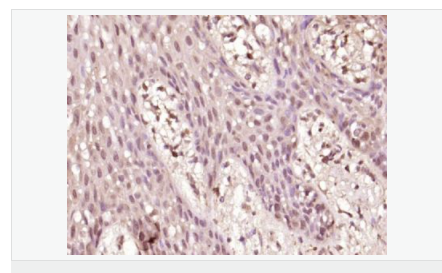

交叉反應:Human,Mouse,Rat(predicted:Dog,Pig,Cow,Horse,Sheep) 推薦應用:WB,IHC-P,IHC-F,IF,Flow-Cyt,ELISA

產品應用WB=1:500-2000 ELISA=1:5000-10000 IHC-P=1:100-500 IHC-F=1:100-500 Flow-Cyt=1μg /test IF=1:100-500 (石蠟切片需做抗原修復)